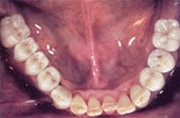

Festsitzende Brücken und Kronen aufgesetzt

Ersatz der Unterkiefer-Seitenzähne beidseits mit natürlich aussehenden, festsitzenden Brücken und Kronen auf Implantaten.

Fehlen mehrere Zähne, so spricht man vom teilbezahnten Kiefer. Solche größeren Zahnlücken konnten früher oftmals nur mit herausnehmbaren Teilprothesen geschlossen werden, wenn eine Brückenversorgung nicht mehr möglich war. Implantate erlauben, die Lücke mit einer implantatgetragenen festsitzenden Brücke zu schließen, ohne herausnehmbare Prothesen und ohne Abschleifen gesunder Nachbarzähne.